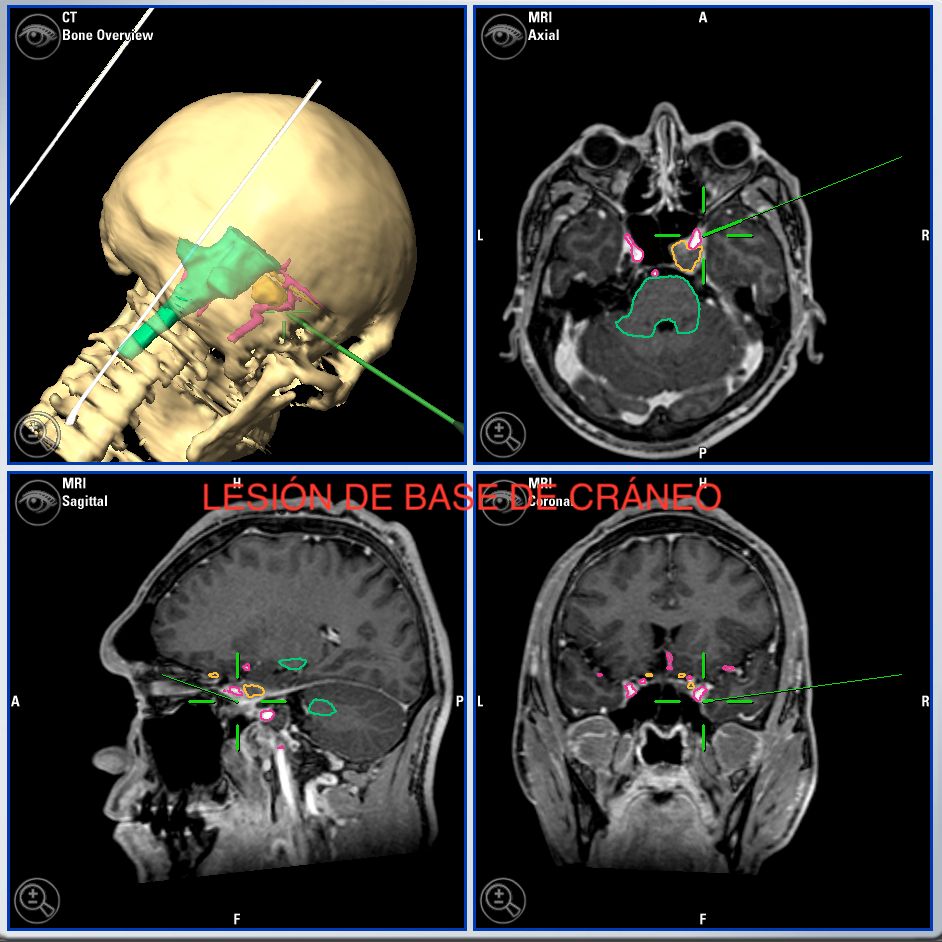

Microcirugía de base craneal